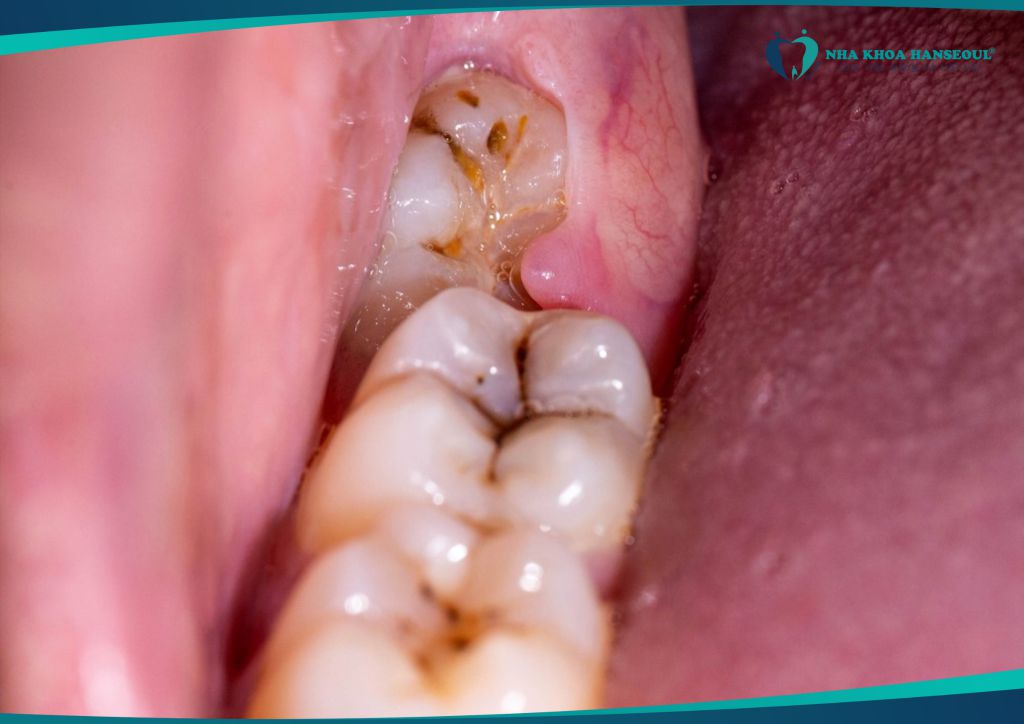

2.1 Gây sâu răng số 7 – răng hàm quan trọng

Răng số 8 mọc lệch thường đâm vào răng số 7, tạo thành khe hẹp khó vệ sinh. → Thức ăn mắc lại lâu ngày dẫn đến sâu răng số 7, viêm tủy, thậm chí mất răng vĩnh viễn.

2.2 Viêm lợi trùm – nhiễm trùng lan rộng

Răng khôn chỉ mọc một phần (mọc kẹt), mô nướu phủ bên trên dễ bị vi khuẩn tấn công, gây:

- Sưng tấy, đau nhức dữ dội

- Sốt nhẹ, nổi hạch

- Hơi thở có mùi hôi

Trường hợp nặng có thể lan rộng sang má, vùng cổ, gây áp xe nguy hiểm.